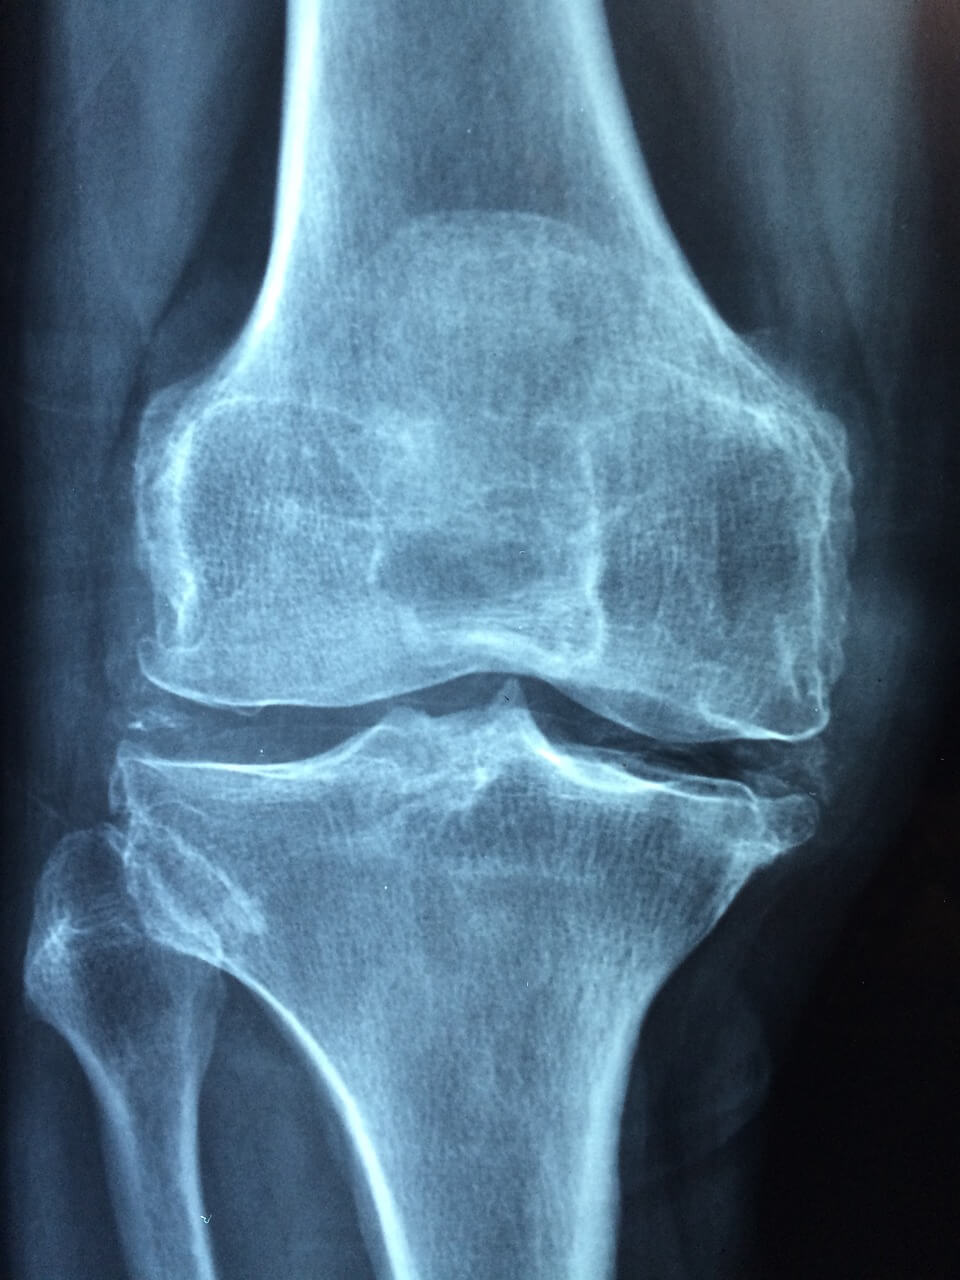

1. 자가 면역 기능 장애

류마티스 관절염은 자가 면역 질환으로, 면역 체계가 건강한 관절 조직을 잘못 공격하여 염증과 통증을 일으킵니다.

류마티스 관절염이 진행되면 관절의 이동성과 유연성이 제한될 수 있습니다.